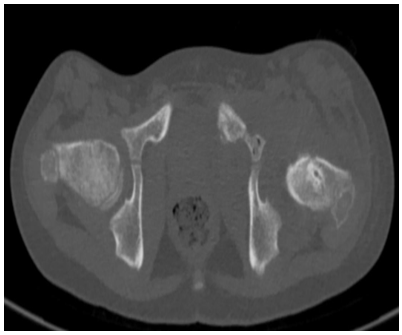

Case Report

Hip Septic Arthritis: Complications Including Multiple Collections and Osteonecrosis

A Guennouni, C Abourak, S Bahha, S El Haddad, N Allali and L Chat. 13(12): 01-04.